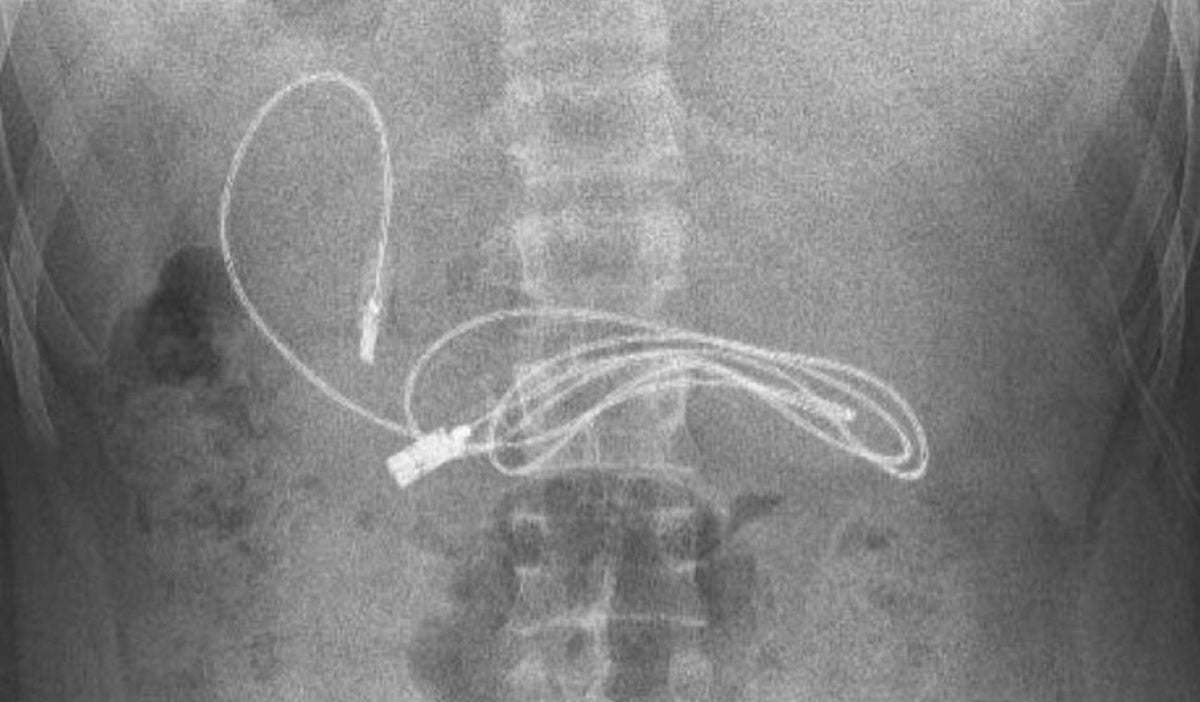

Un joven turco de 15 años tuvo que ir al médico luego de sufrir fuertes dolores de estómago. Cuando llegó al hospital, los trabajadores de salud le realizaron varios exámenes para saber qué era lo que le estaba generando el malestar.

Pero algo curioso descubrieron los médicos, ya que encontraron un cable USB y una goma para el cabello en su interior.

Para poder extraer estos objetos, el joven fue intervenido quirúrgicamente. El gastroenterólogo que realizó la operación, publicó en sus redes sociales imágenes de hallazgo.

El doctor Yasar Dogan aseguró que se tuvo que hacer una endoscopia para poder llegar de una manera más fácil a los objetos, pero que fue complicada.

“Tuvimos dificultades para quitar el cable, ya que un extremo había pasado al intestino delgado". A pesar de las dificultades, la intervención fue un éxito, pues el paciente "fue enviado a casa con buena salud", afirmó.

Por el momento se desconocen las razones por las que terminaron el cable USB y la goma para el pelo en el cuerpo del joven.